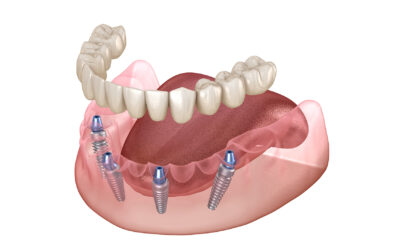

All-On-4 Dental Implants: A Streamlined Path to a Confident, Lasting Smile

Imagine replacing a full arch of missing or failing teeth with a smile that looks natural, feels secure, and functions like your own, often in a single,...